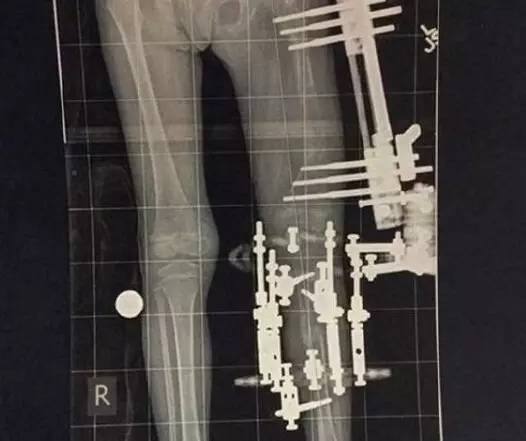

要在截肢和每日折斷左腿之間作選擇,相信比著任何父母都難以決定,但為了女兒的將來,Elsie的媽媽選擇了後者,故此,Elsie再次接受手上術,在股骨和脛骨的中間裝入一個外部固定支架,並釘入10支釘,每日Elsie媽媽每日都會定時,動按鈕目的是將脛骨與股骨分開約一毫米,以便骨頭生長。